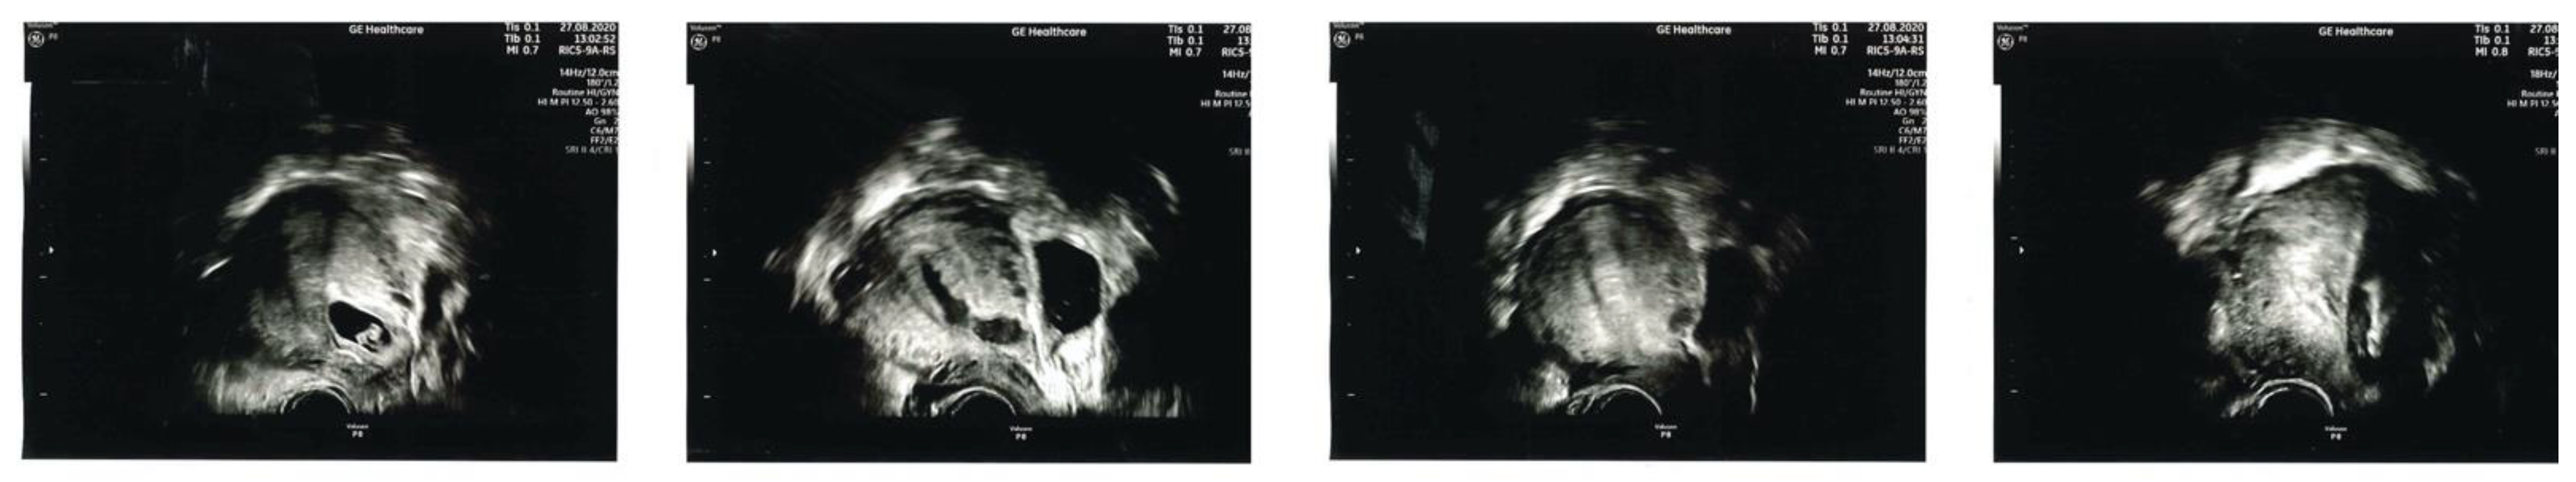

Seventeen patients elected to have surgical management. Fifteen opted for transrectal ultrasound guided suction evacuation (Figure 3). 5/15 required cerclage and balloon tamponade and three required cerclage tamponade only.

Figure 3. Intraoperative transrectal ultrasound guidance is crucial to ensure complete evacuation of the uterine cavity and caesarean scar niche.